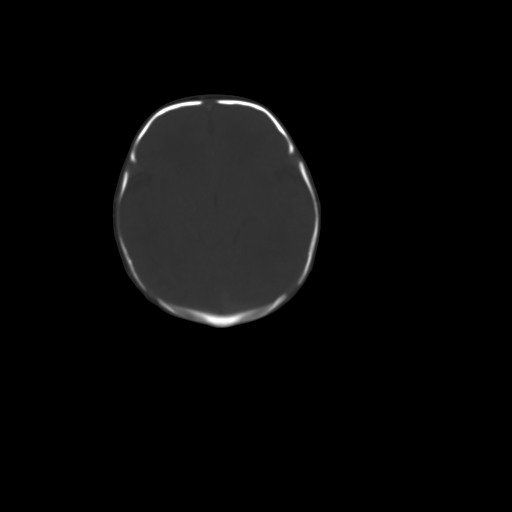

男,12天,自然分娩,其母发现右顶部头皮包块逐渐增大。

右顶部头皮血肿

右顶部头颅血肿(骨膜下血肿)

右顶骨呈膨胀性改变,骨纤维结构不良?

右顶部头皮血肿,可能是产道挤压所致。以后会慢慢恢复。

鉴别:骨膜下血肿,一般为产伤,应用产钳之类的吧